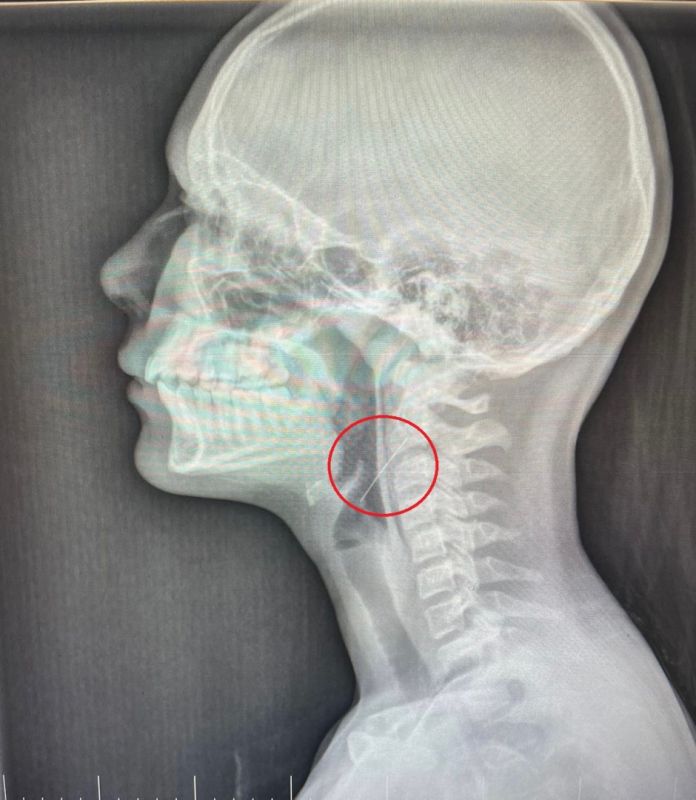

Девочка держала иголку в зубах, когда вешала гирлянду. При движении она случайно проглотила иглу. Почти сразу подросток почувствовала невыносимую боль и тошноту. Ей потребовалась помощь врачей.

Доктора оперировали ребёнка всю ночь. Они провели прямую ларингоскопию, в ходе которой обнаружили, что игла вонзилась в правую стенку глотки.

Врачи удалили инородное тело. Пациентку уже выписали. Её жизни ничего не угрожает.